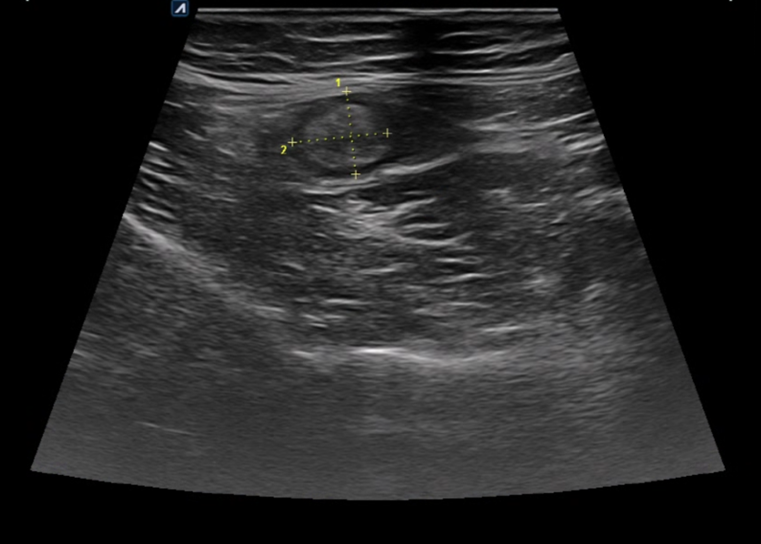

생리통으로 오인하여 내원한 복통 환자의 초음파.

하복부의 장관 부종이 확인됩니다.

골반에 복수 의심 소견이 관찰됩니다.

*난소종양 의심 소견 확인되어 대학병원 의뢰되었습니다.